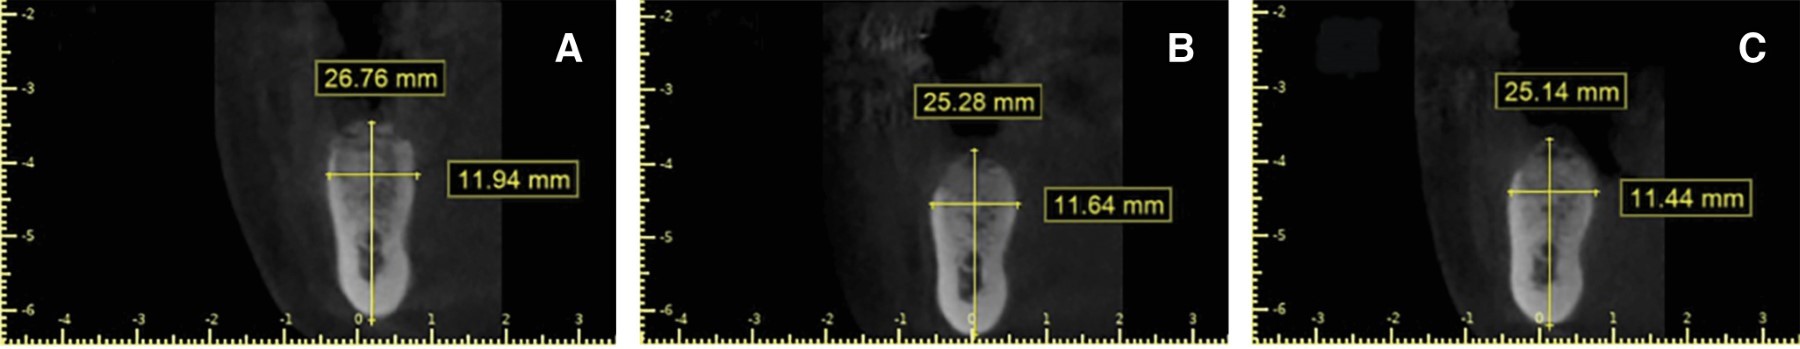

Figure 2